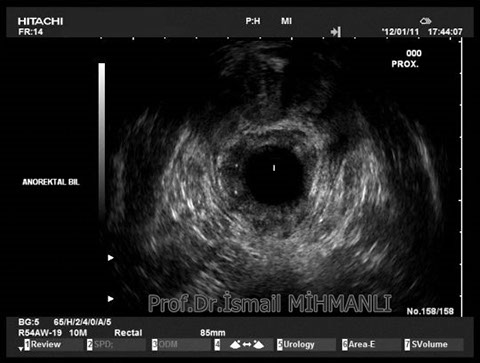

PERİANAL FİSTÜLLER Perianal fistül ve abselerin intersfinkterik anal bez iltihabından kaynaklandığı düşünülmektedir. Crohn hastalarında perianal enflamatuvar hastalık sıktır. İntersfinkterik mesafedeki enfeksiyon yukarıda rektuma, aşağıda cilde, yanlarda dış sfinkteri geçerek iskiyoanal mesafeye uzanabilir. Primer fistülün sfinkterler ile ilişkisini ve abse veya sekonder dal varlığını ameliyat öncesi bilmek, tedavi planı açısından önemlidir. İskiyoanal ve iskiyorektal mesafe tutulmamışsa hastalık daha kolay tedavi edilir. Bu mesafelerde abse veya sekonder bir dal varsa fistül komplekstir ve tedavisi kompleks olmayan fistüle göre değişik olabilir. Bundan dolayı, primer fistül traktı anatomik yerleşimine göre geleneksel olarak sınıflandırılır. Bu sınıflama dörde ayrılır: 1- İntersfinkterik (iç ve dış sfinkter arasında), 2- Transsfinkterik (dış sfinkteri geçerek iskiyoanal veya iskiyorektal mesafeye ulaşmış), 3- Suprasfinkterik (intersfinkterik plandan yukarı doğru uzanan traktüs puborektal kasın Genel Gaz ve Dışkı Kaçırma (Anal İnkontinans) Perianal Fistüller Rektal Tümörler Anal Tümörler Kabızlık Yazılarımız üstündeki bir seviyeden yana kıvrılarak tekrar aşağıya iskiyoanal mesafeye uzanmış), 4- Ekstrasfinkterik (sfinkterlerin dış tarafında rektumdan direkt olarak perianal cilde uzanan traktüs). Endoanal ultrason ile hem primer fistül, hem de varsa sekonder dal ve abse doğru bir şekilde tanınır. Endoanal ultrason ile fistülün anal kanala açılan kısmını (iç uç) görmek kolaydır. Bu hastalarda sfinkter defektlerine de rastlanmaktadır. Sfinkter defekti endoanal ultrason ile kolaylıkla tespit edilir. (bkz. anal inkontinans) Perianal fistül şikayeti olan hastaların az kısmında endoanal ultrason ile bir şey görülemez ise endoanal ultrason probuna ek olarak lineer prob ile anal kanal çevresine bakmak yararlıdır. Çünkü anal kanal bileşenlerinin uzağındaki bir enflamasyon ancak bu problar ile tanınabilir.

İntersfİnkterİk fİstül TRANSSFİNKTERİK FİSTÜL